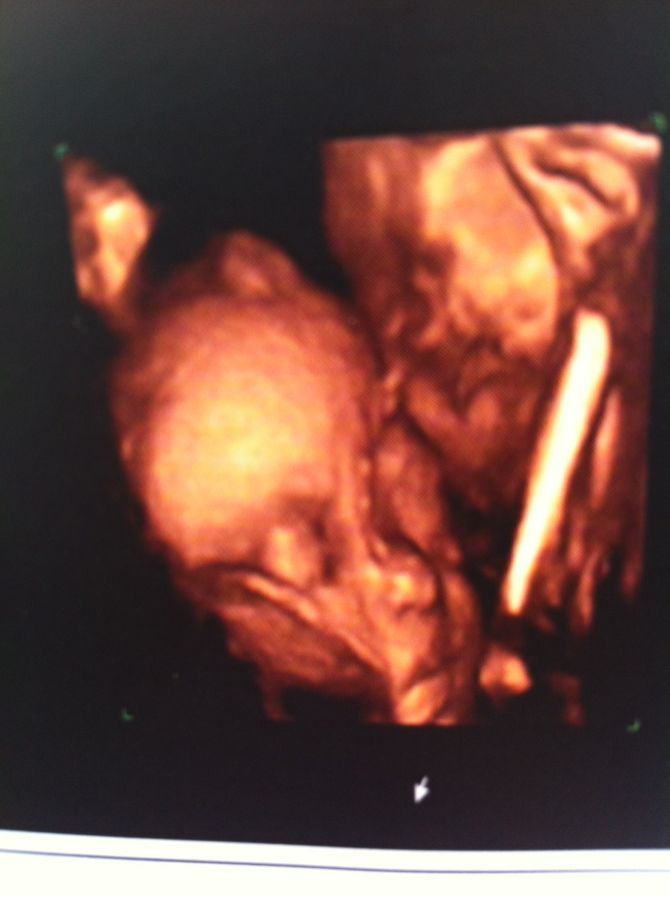

六个月胎儿三维彩超,请帮忙看一下

病情描述(发病时间、主要症状等):6个月的时候做的三维彩超图,怎么我家宝宝没鼻子呢?医生说鼻子的部位是脐带,一直延伸到头顶,那不就是一点鼻梁骨都没有嘛?医生倒是没说有啥缺陷,可六个月也该长出鼻梁骨了吧?郁闷

你好!有鼻梁的,是脐带或光线遮挡造成的图像不清晰,胎儿是六个月开始长头发的,行指孕妇一般会出现胃口烧心等现象,衣服要宽松柔软,要多吃新鲜水果蔬菜,碗吉以保证大便通畅,夜间睡觉要抬高上身,以减少食物返流。 注意合理饮食,慎食高脂肪肥腻食物、浓茶、咖啡、巧克力、芳香性调料及酸性、辛辣刺激性食物,进食不宜过饱,特别是晚餐更忌饱食,可在睡前2~3小时进餐,以免腹内劣峡串压升高。 祝健康好孕!

没长胎毛呢。还有医生说的不是没有鼻子,是鼻子被脐带挡住了吧。